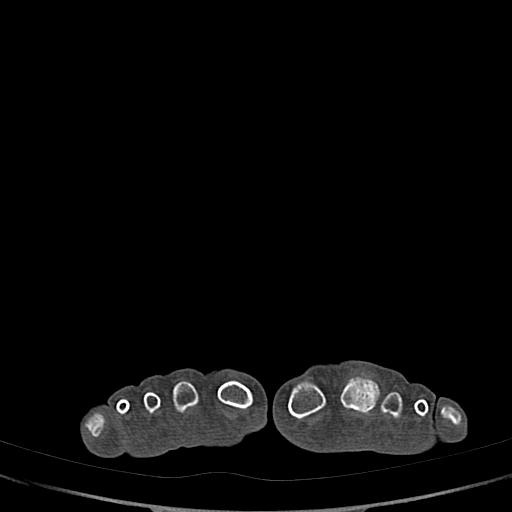

标题: CT13415:M72Y,跖趾关节病变,请会诊 [打印本页]

标题: CT13415:M72Y,跖趾关节病变,请会诊

男72岁左侧跖趾关节肿痛15年,查压痛。

骨软骨瘤可能性大,请上传x光片.

考虑退行性骨关节病。